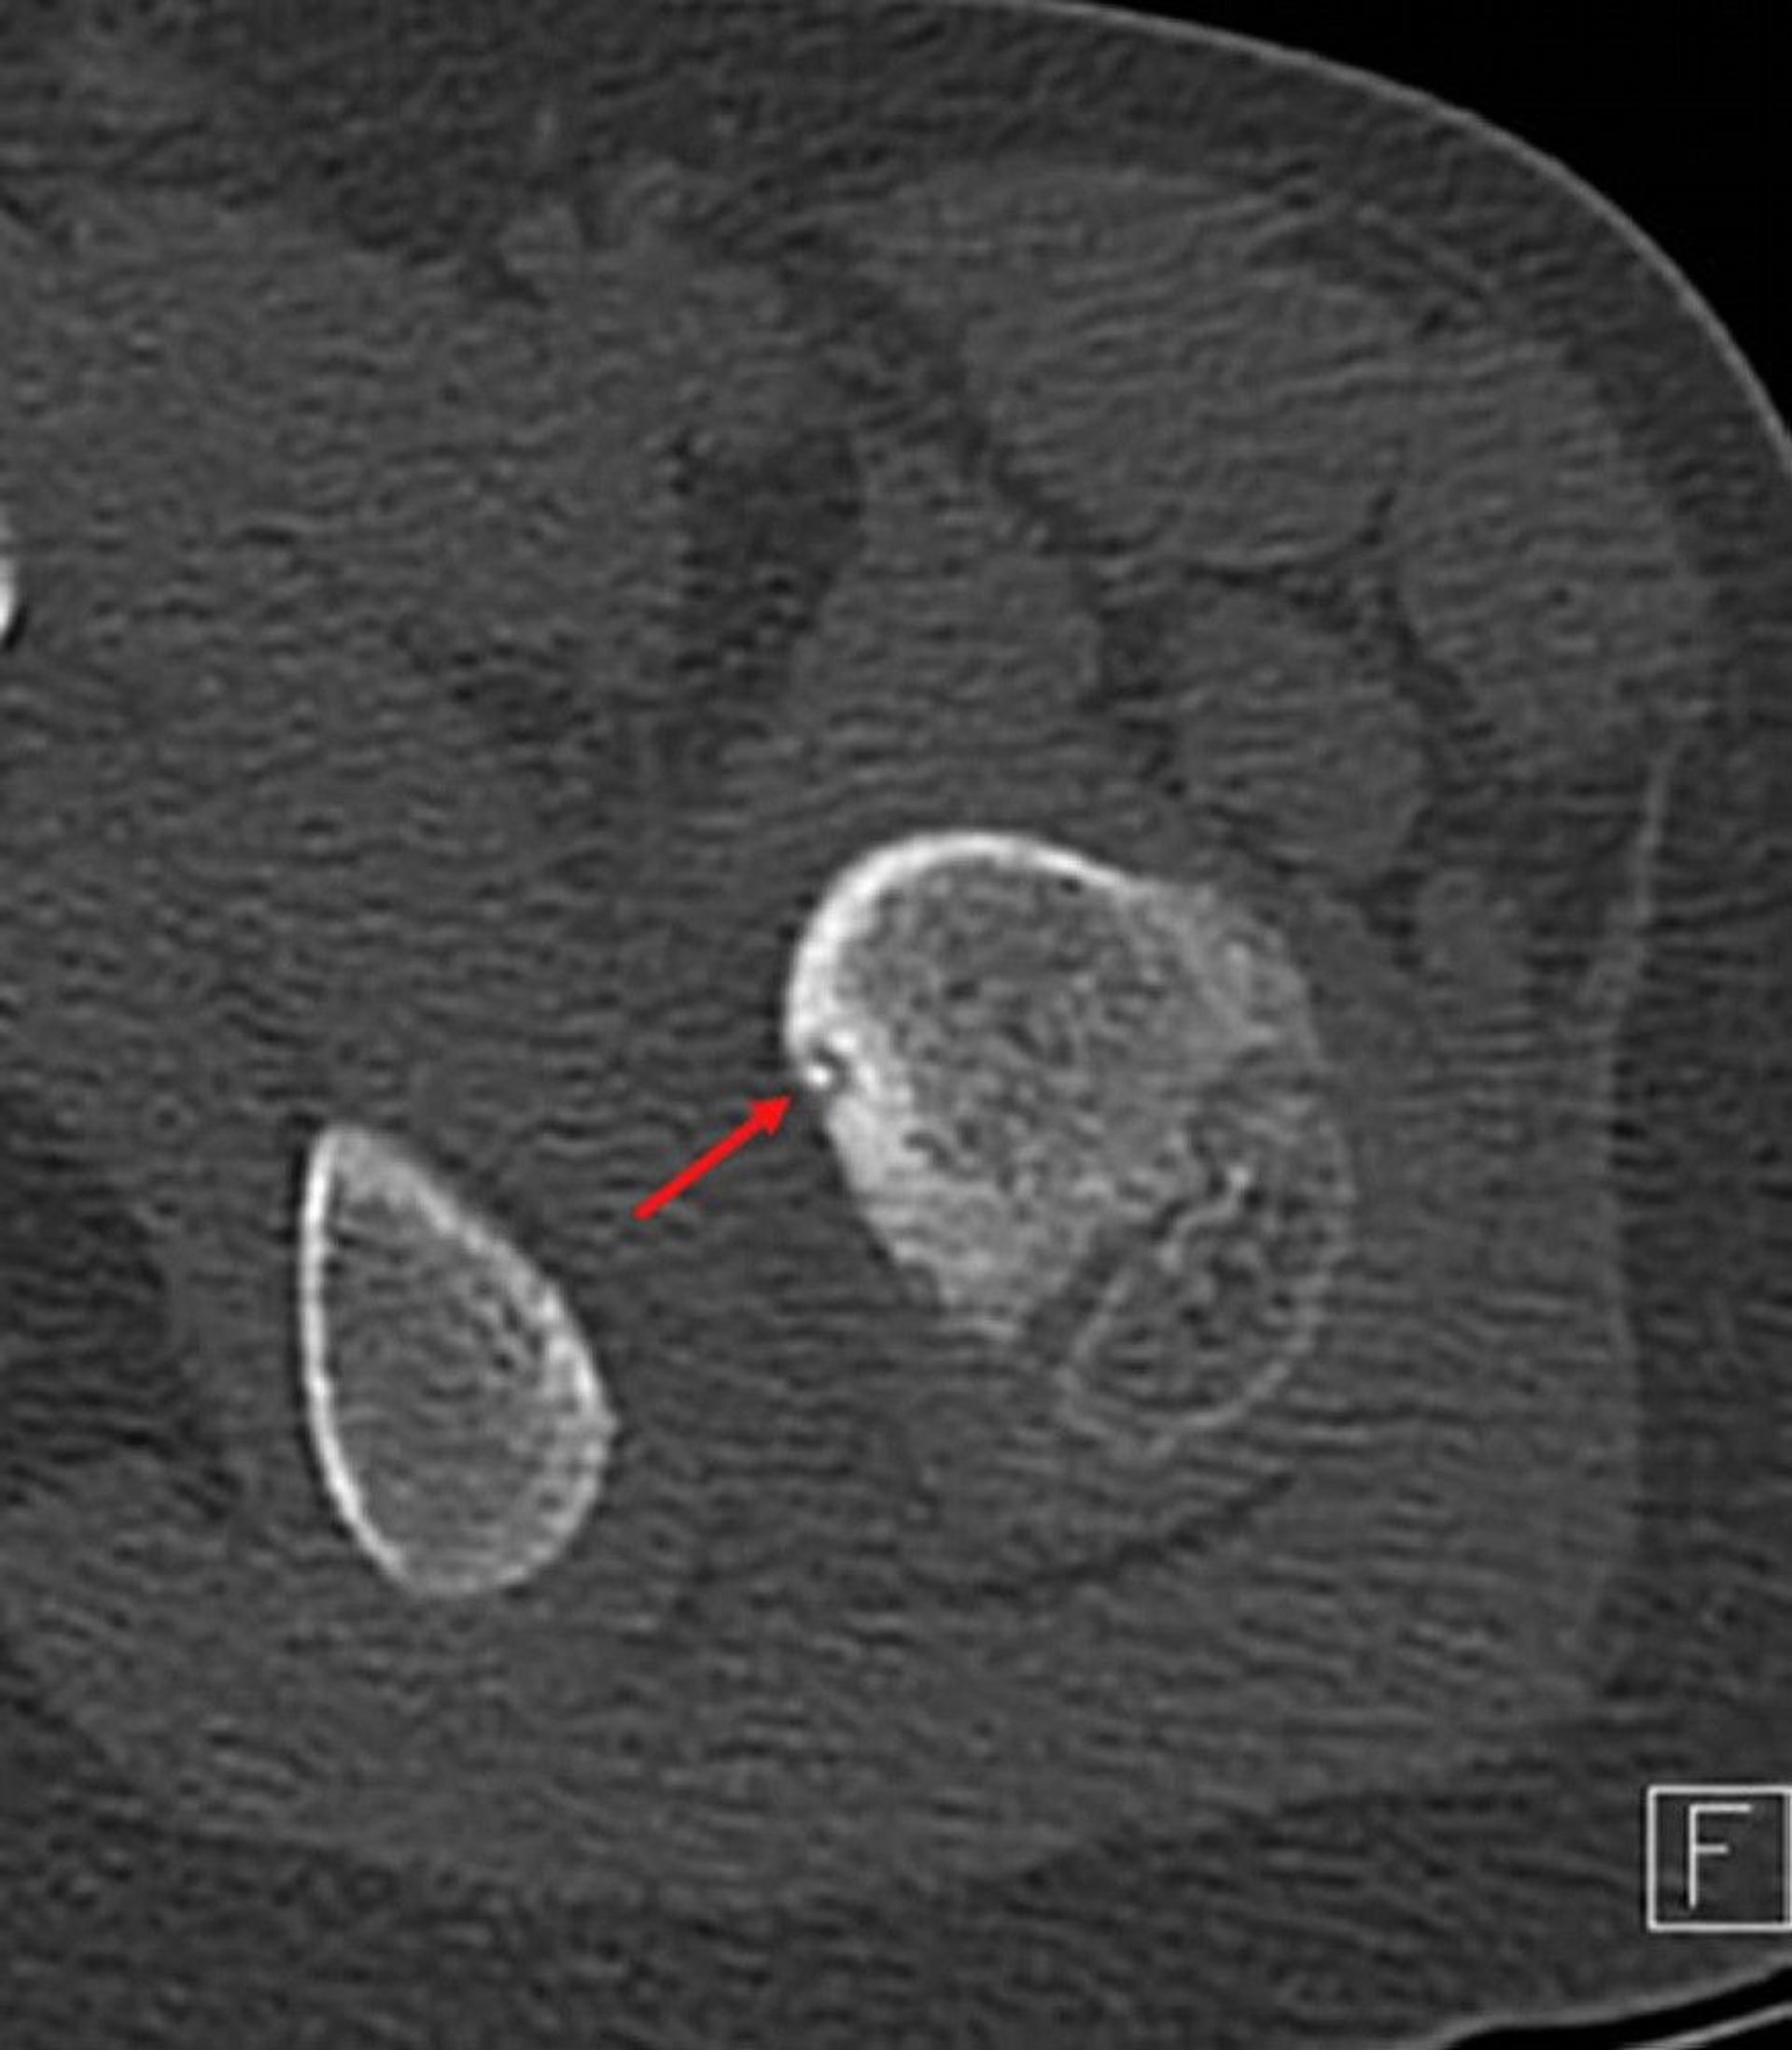

Axial CT image of the proximal femur (adjacent bone is pelvic ramus) demonstrating the typical radiolucent nidus with central calcification (arrow) and surrounding reactive rim in a child with left hip pain.

Image courtesy of Michael J. Joyce, MD, and Hakan Ilaslan, MD.